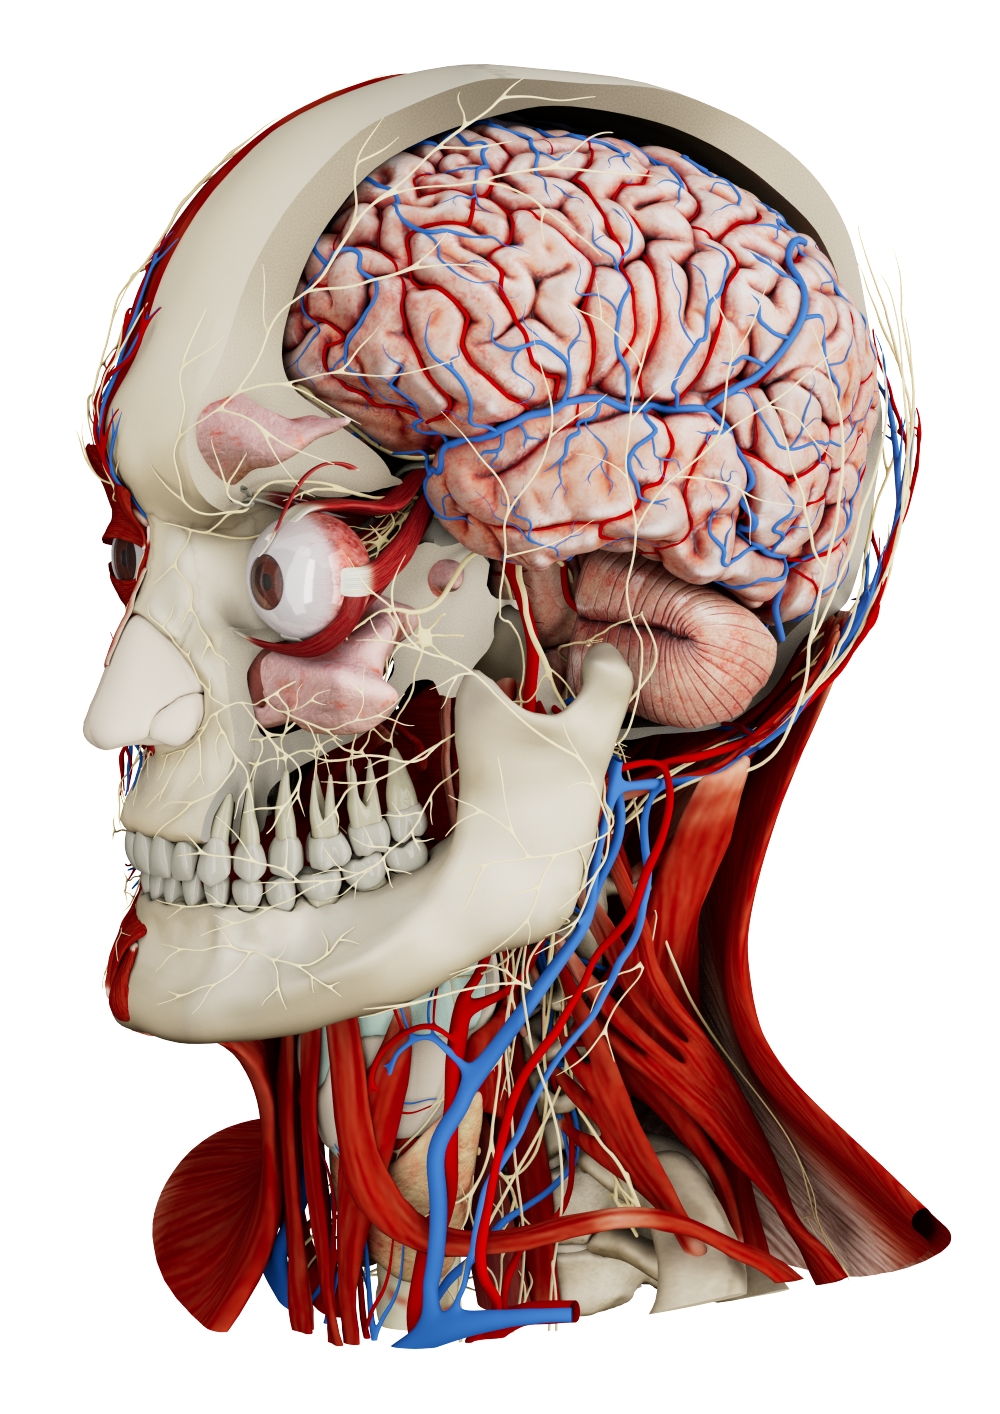

AI segmentation and digital twins in medical education

As 3D technologies continue to evolve in medicine, this study demonstrates how patient-specific virtual models are beginning to reshape medical education with Medicalholodeck.